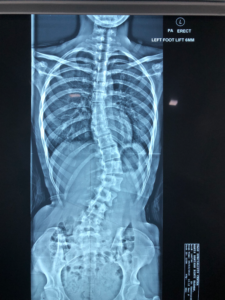

Scoliosis can be divided into primary and secondary, of which primary (unexplained cause) accounts for 80%. Recent studies have found that primary scoliosis is mostly genetic inheritance, and a few are environmental factors. Most patients do not experience any pain, and only a few severe patients have difficulty in breathing because their lungs are squeezed by the curved spine. Usually, postural assessment and Adam's test can be used to check whether there is scoliosis, and X-ray can determine its severity. The spine will curve to the left or right, accompanied by rotation and tilting front and back with "3D" abnormalities, which are prone to continue to deteriorate during adolescence (bone growth period), so it is common in adolescents who are 10 years old to fully-grown adolescent.

Generally, the severity of scoliosis is affected by two main factors: the degree of the angle and the age of bone development. There are different treatment options according to its different severity. The following is a brief description: